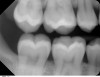

Radiografie cu film mușcat (Bitewing)

Pun în evidență coroanele dinților, arătând în același timp dintele de sus și cel corespunzător de jos. Aceste radiografii sunt folosite pentru urmărirea mușcăturii, a cariilor dintre dinți și a pierderilor de masă osoasă.